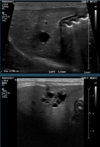

What is shown in these images?

ultrasound of the gall bladder:

-top: anechoic bile

-bottom: sludge (normal in dogs)